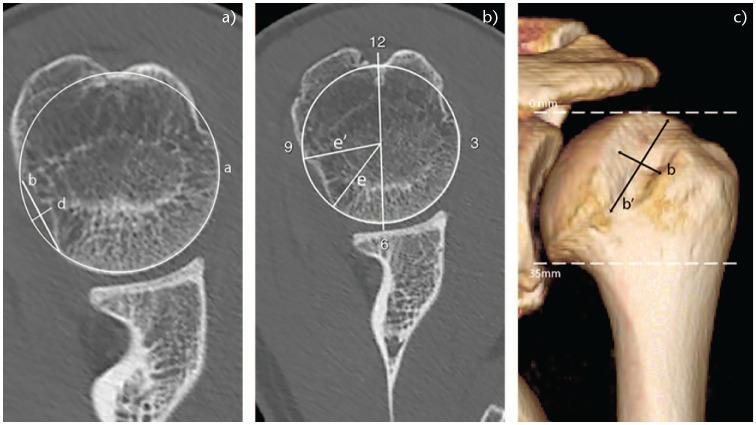

The coexistence of glenoid and humeral head bone defects may increase the risk of recurrence of instability after soft tissue repair.Revealed factors in medical history such as male gender, younger age of dislocation, an increasing number of dislocations, contact sports, and manual work or epilepsy may increase the recurrence rate of instability.In physical examination, positive bony apprehension test, catching and crepitations in shoulder movement may suggest osseous deficiency.Anteroposterior and axial views allow for the detection of particular bony lesions in patients with recurrent anterior shoulder instability.Computed Tomography (CT) with multiplanar reconstruction (MPR) and various types of 3D rendering in 2D (quasi-3D-CT) and 3D (true-3D-CT) space allows not only detection of glenoid and humeral bone defects but most of all their quantification and relations (engaging/not-engaging and on-track/off-track) in the context of bipolar lesion.Magnetic resonance imaging (MRI) is increasingly developing and can provide an equally accurate measurement tool for bone assessment, avoiding radiation exposure for the patient. Cite this article: 2020;5:815-827. DOI: 10.1302/2058-5241.5.200049.

肩胛盂和肱骨头骨缺损并存可能会增加软组织修复后不稳定复发的风险。病史中显示的因素,如男性、脱位时年龄较小、脱位次数增加、接触性运动、体力劳动或癫痫,可能会增加不稳定的复发率。体格检查中,阳性骨恐惧试验、肩部运动时有卡顿和摩擦音可能提示骨缺损。前后位和轴位视图有助于检测复发性前肩关节不稳定患者的特定骨病变。计算机断层扫描(CT)结合多平面重建(MPR)以及二维(准三维CT)和三维(真三维CT)空间中的各种三维渲染,不仅可以检测肩胛盂和肱骨骨缺损,最重要的是可以在双极病变的背景下对其进行量化以及确定它们之间的关系(嵌合/不嵌合以及轨迹内/轨迹外)。磁共振成像(MRI)发展迅速,可为骨评估提供同样准确的测量工具,避免患者受到辐射暴露。引用本文:2020;5:815 - 827。DOI:10.1302/2058 - 5241.5.200049。